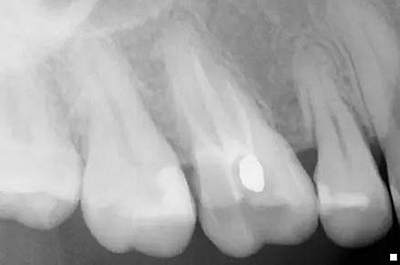

原始x線影像

X線攝片狀況。